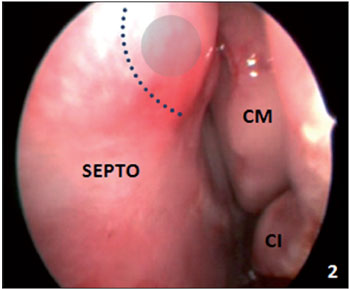

CASE STUDY #1A 57-year-old female patient sought advice from the Specialized Service in Otolaryngology in June 2008, complaining of a frontal headache that had been present for the last year. The patient reported previous drug treatments for sinusitis including azithromycin for 5 days, amoxicillin for 10 days, and a combination of amoxicillin and clavulanate potassium for 10 days. However, she always experienced recurrence and progressive worsening of her symptoms. Examination with video-endoscopy showed hypertrophy of the lower and middle turbinates bilaterally associated with septal deviation in the left nasal cavity. A computed tomography (CT) scan of the paranasal sinuses and nasal cavity in the axial, coronal, and sagittal planes with a bone window of 2500-3500 rads was requested, which identified pneumatization of the crista galli with mild mucosal thickening in the interior (Figure 1). This finding indicated endoscopic surgery through the transseptal approach in the left nasal cavity for drainage and cleaning of the pneumatized crista galli (Figure 2).

Figure 2. Video-endoscopic visualization of the left nasal cavity showing the septal incision site and opening of the bone wall of the pneumatized crista galli. SEPTO = nasal septum; CM = middle turbinate; CI = inferior turbinate.